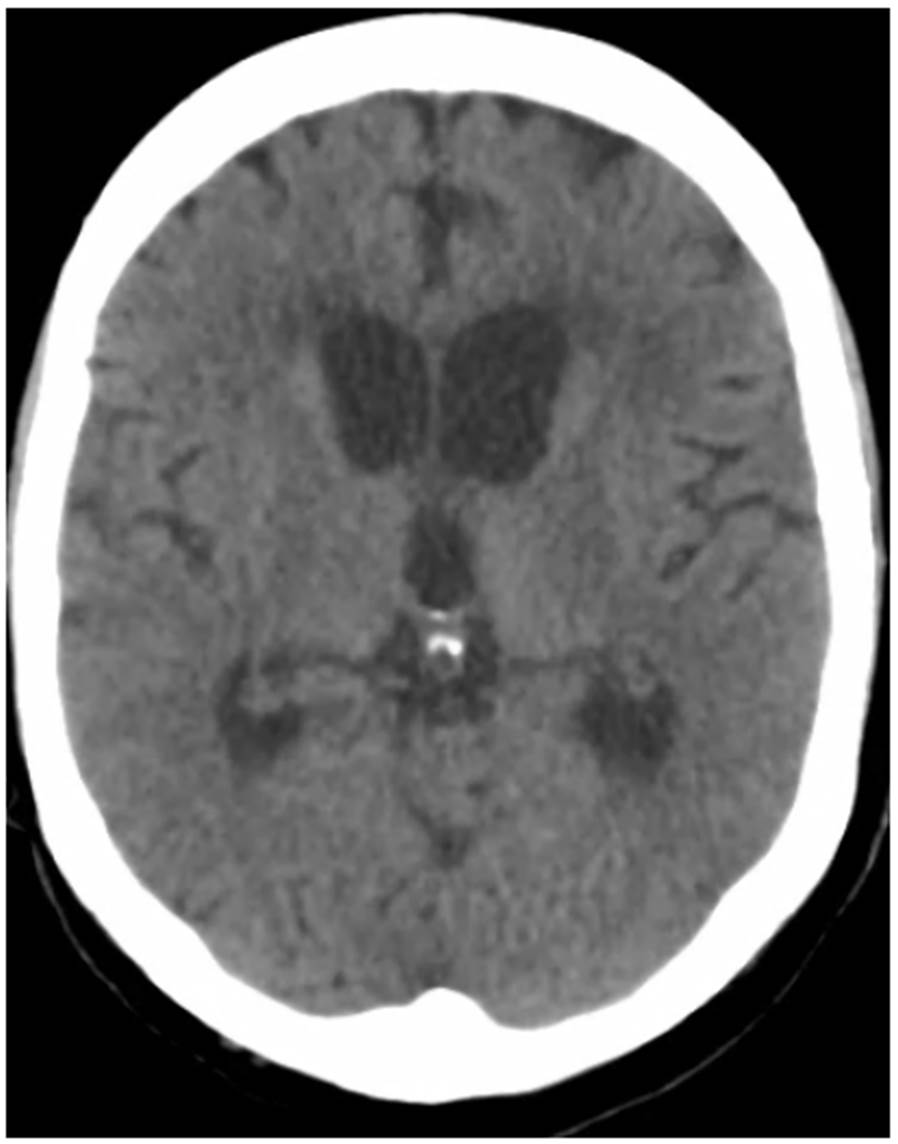

Figura 1 Tomografía de cráneo que muestra aumento de tamaño de los ventrículos laterales y el tercer ventrículo, indicativo de hidrocefalia no comunicante

En la segunda TC de cráneo se encontró hidrocefalia no comunicante (figura 1). En la punción lumbar, se obtuvo un líquido raquídeo de aspecto turbio, cuya viscosidad no permitió medir la presión de apertura; las proteínas estaban en 1.000 mg/dl, los leucocitos en 2 por mm3, la glucosa en 33 mg/dl y el antígeno de Cryptococcus dio positivo. En el cultivo del líquido cefalorraquídeo, se detectó C. neoformans. Además, una tomografía de tórax de alta resolución demostró compromiso nodular multilobar (figura 2).

En cuanto a las imágenes, la TC de cráneo puede evidenciar hidrocefalia, nódulos múltiples, masa que ocupa espacio, aunque también puede no revelar ninguna anormalidad.